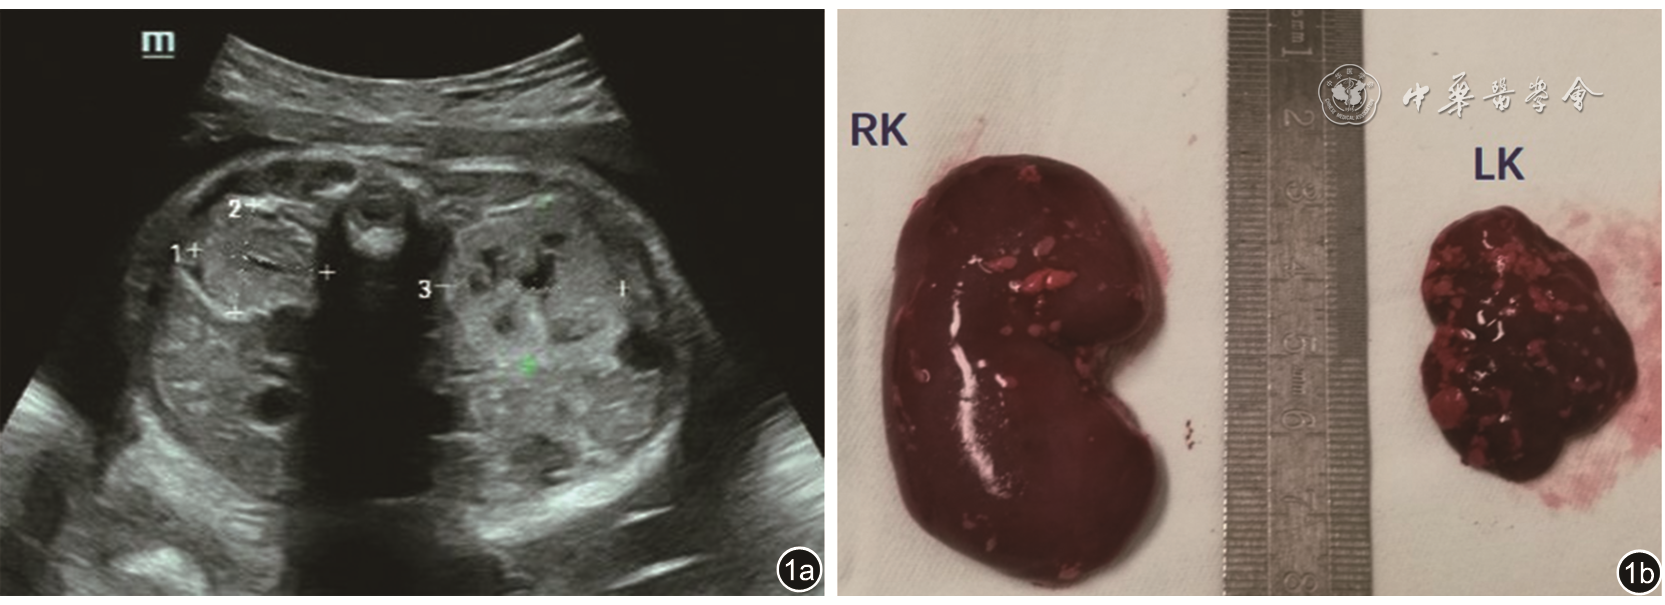

图1 孕33周胎儿肾超声声像图。图a超声声像图示右侧肾体积明显增大,皮髓质分界清晰,皮质回声增强;左侧肾体积轻度增大,皮髓质分界模糊,实质可见多发大小不等的囊性结构;图b为胎儿肾大体观

注:RK为右肾,LK为左肾

图4 孕28周胎儿肾超声声像图。双肾横切面显示体积明显增大,回声增强,皮髓质回声倒置,髓质回声高于皮质回声。基因检测为PKHD1基因突变